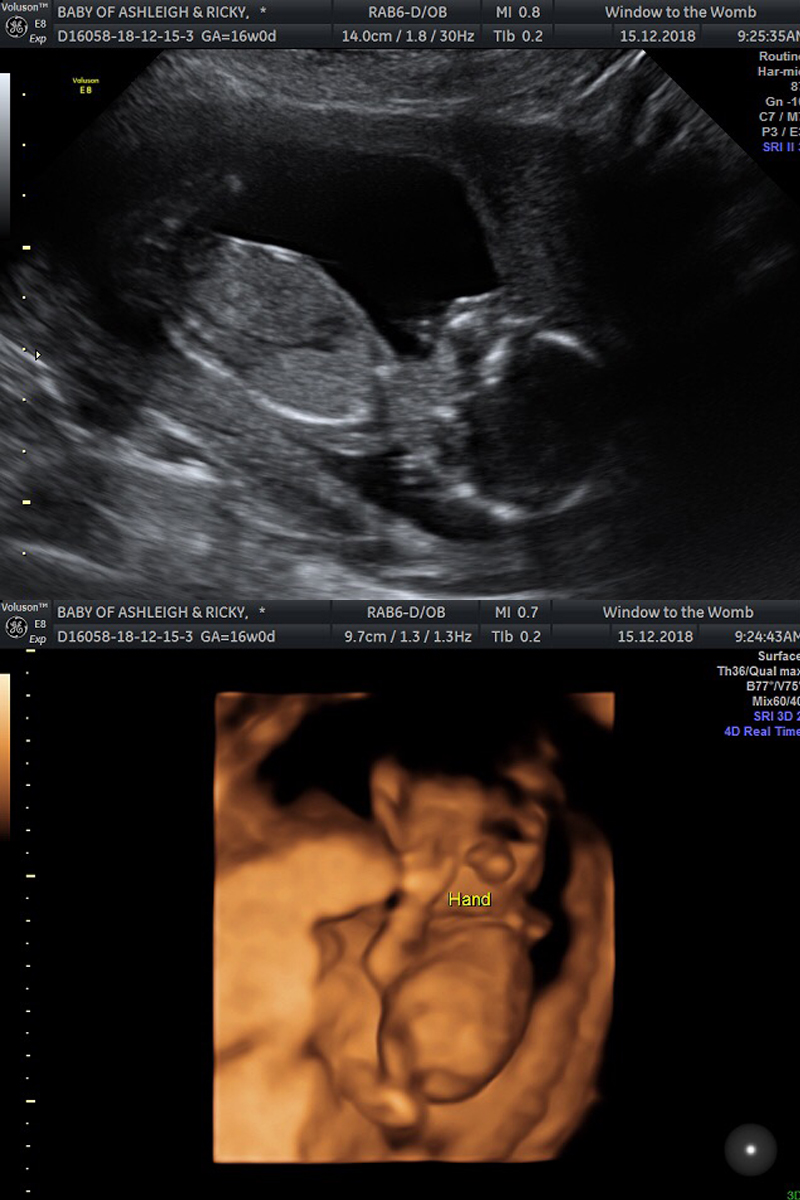

Onto the scan itself incase anyone is interested in reading more about early gender scans. We had ours at 16 weeks.

I cannot recommend Window To The Womb private clinics enough (*not sponsored). You are made to feel welcome and special the moment you walk in and the scan itself is made to be much more special in my opinion. We had the same sonographer as our early 6 week scan, so it was nice to see a familiar face and the setting is super comfortable and relaxing; spa like music and low, warm lighting and a sofa provided for up to 5 guests that you are allowed to bring.

The package we paid for gave us a gender reveal, health check and a sneak preview in 4D - something we was all really looking forward to.

Baby is a little wriggler and kept moving around, mostly standing on this head! However, these two photos are my favourite as you can really see details. In the 4D photo, it sort of looks like a huge nose, but it's actually his two hands on his face. You can see a thumb so clearly!

My beautiful boy.